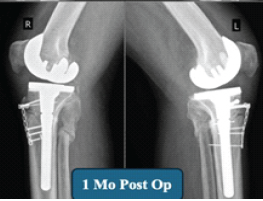

Wheelchair to Walking: Quadruple Arthroplasty of Hip and Knee Joints in a Patient with Severe Ankylosing Spondylitis

Remington C. Crossnoe , Varun M. Trivedi , Sterling J. DeShazo , Reagan L. Crossnoe ………………………………p.227-232